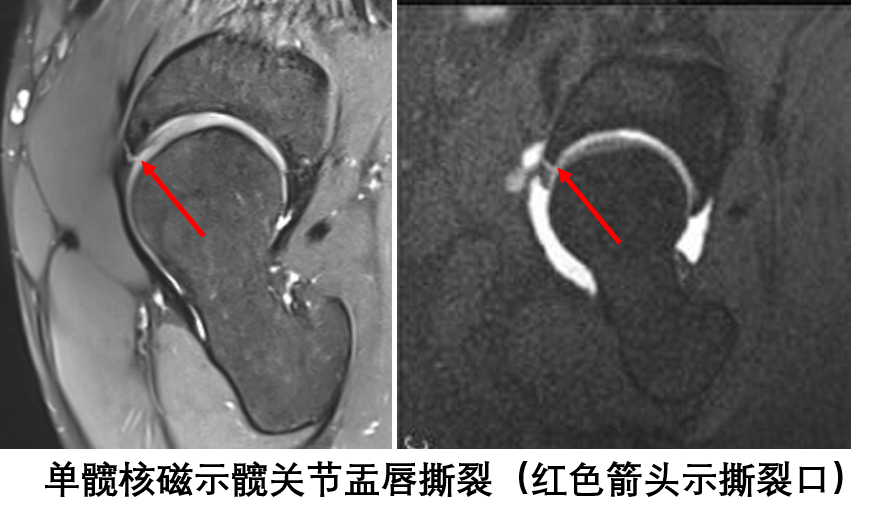

王先生是一位运动爱好者,在体育活动中不慎滑倒导致髋部扭伤,随即出现髋关节疼痛肿胀,经过休息、理疗处理后髋关节疼痛感有了很大缓解,但每次蹲下起立时髋关节里总是发生一声闷响,偶尔还会髋关节“卡锁”感。经过多家医院就诊,却一直找不到病因。为此,王先生来到深圳市第二人民运动医学科就诊,经仔细体查和单侧髋关节核磁检查最终找到了困扰王先生的病根——髋关节盂唇撕裂,并接受了髋关节镜微创手术治疗,经过一段时间的康复练习已经恢复如常。

髋臼盂唇撕裂后早期需要拄拐使髋关节不负重,辅助止痛和理疗,促进盂唇的自身修复。但是髋关节盂唇就行膝关节半月板一样,血管分布相对匮乏,自身愈合能力有限。所以,一旦诊断为髋臼盂唇撕裂,应该积极手术治疗,最大程度的修复盂唇,恢复“密封圈”的功能。目前诊断髋关节盂唇撕裂主要依据单髋核磁检查。